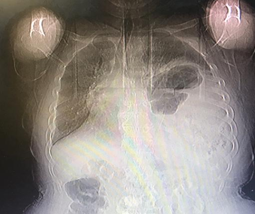

The patient underwent surgery, and laparotomy was performed with an upper midline incision. The exploration showed a large defect measuring 10×15 cm in the posterolateral part of the left diaphragm, through which the left kidney, spleen, small intestinal loops, and part of the colon were displaced into the thoracic cavity. Adhesions were released, and all viscera were pulled down to the abdomen without any problem (Figure 3). The defect site was repaired with a dual mesh so that the mesh was sewn to the diaphragm and chest wall with 0-1 prolene suture with sufficient overlap. A 28-inch chest tube was inserted into the left thorax. The Postoperative chest X-ray is shown in Figure 4. The patient was in the ICU for 1 day after surgery and 3 days in the ward.

Figure 4 Postoperative chest X-ray.